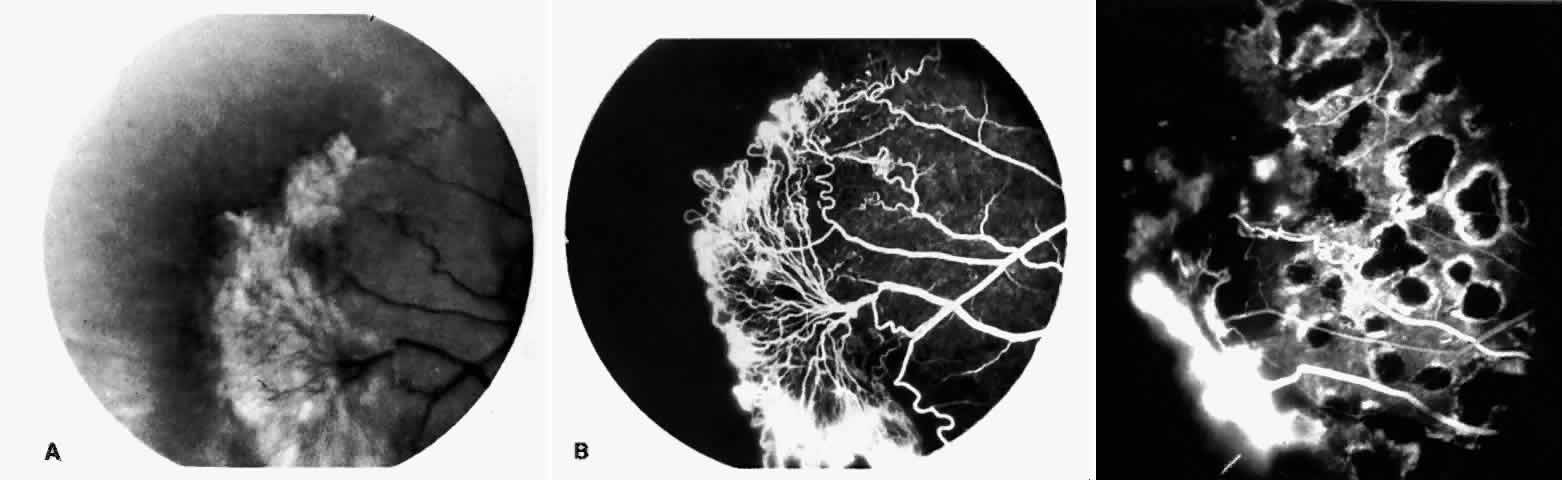

STAGE III: PRERETINAL NEOVASCULARIZATION (PROLIFERATIVE SICKLE RETINOPATHY). “Sea fan”-shaped neovascularization typically develops on the venular side of an arteriolar-venular anastomosis, mimicking the normal development of retinal capillaries (Fig. 24).125 A lowered oxygen tension and angiogenic factors released on the venular side may be the stimulus for neovascular growth.125,126 In most instances, the direction of growth is toward the ora serrata, from the perfused retina toward the nonperfused retina. Presumably, this represents an abortive attempt to revascularize the nonperfused retina, initiated by vasoproliferative factors.

Fig. 24. A. Photograph of the peripheral retina, demonstrating several small fibroglial membranes. B. Fluorescein angiogram corresponding to A, showing multiple arteriolar-venular anastomoses with early sea fan formation. C. Photograph of the same area 2 years later demonstrates more fibroglial membranes. D. Fluorescein angiogram corresponding to C shows new sea fans caused by an arteriolar-venular anastomosis (curved arrow). Large arrow (A through D) identifies corresponding arteriolar bifurcation.

The characteristic neovascular lesions of PSR are called sea fans because they resemble the marine invertebrate Gorgonia flabellum.70 They tend to occur more commonly in the temporal periphery, but they have been reported to occur in the temporal macula in the presence of extensive nonperfusion.130,133 Initially they grow on the surface of the retina, but they often become elevated into the vitreous and adhere to a partially detached posterior hyaloid.114 It may be difficult to visualize small sea fans ophthalmoscopically; however, fluorescein angiography clearly demonstrates leakage of dye into the vitreous (Fig. 25). The feeding arteriole is usually more tortuous than the draining venule (Fig. 26). Early on, the neovascular lesion is fed by a single arteriole and drained by a single venule, but with time, additional arterioles and venules become arborized within the lesion (Fig. 27).129 Growth of the sea fan often occurs circumferentially, rather than radiallyÜmh- 1Ý, toward the ora serrata. Progressive circumferential growth may lead to neovascular lesions extending around the entire periphery. As it matures, a white fibroglial mantle often covers the neovascular tissue (Color Plate 2B).

PSR is associated with the severe vision-threatening sequelae of sickle cell disease: vitreous hemorrhage (stage IV) and retinal detachment (stage V). These stages are believed to result from transudation of blood components into the vitreous through the incompetent neovascular tissue (Fig. 28). Vitreous fluorophotometry has quantified the leakage from the peripheral neovascularization.134 This leads to premature syneresis and collapse of the vitreous, inducing tractional forces on the retina that lead to vitreous hemorrhage, retinal tears, and tractional and rhegmatogenous retinal detachment. In rare cases, an exudative detachment may occur.

Fig. 28. A. Cross-section of retina shows vitreous adhesions to flat neovascular tissue (stage III proliferative sickle cell retinopathy [PSR]).Fig. 28 (continued).B. Cross-section of retina reveals large clump of neovascular tissue (stage III PSR) protruding from surface of retina into vitreous. C. Cross-section of retina and vitreous. Note large cluster of intravitreous neovascular tissue adherent to vitreous traction bands. (Romayananda N, Goldberg MF, Green WR: Histopathology of sickle cell retinopathy. Trans Am Acad Ophthalmol Otolaryngol 77:652, 1973.)